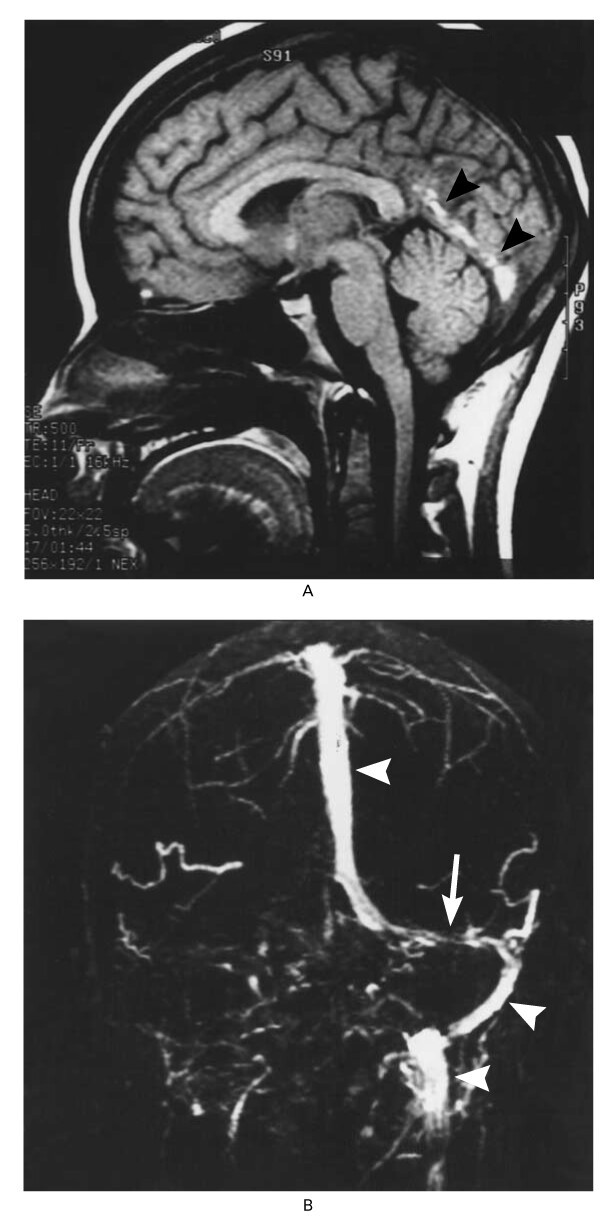

Послеродовое осложнение

Девушка, 18 лет

Через три недели после родов обратилась с жалобами на головные боли, которые беспокоили её в течение недели, а также на тошноту, рвоту и светобоязнь, которые наблюдались в течение двух дней. При осмотре она была заторможенной, у неё наблюдались двусторонний отёк диска зрительного нерва и лёгкий паралич правого отводящего нерва.

Девушка, 18 лет

Через три недели после родов обратилась с жалобами на головные боли, которые беспокоили её в течение недели, а также на тошноту, рвоту и светобоязнь, которые наблюдались в течение двух дней. При осмотре она была заторможенной, у неё наблюдались двусторонний отёк диска зрительного нерва и лёгкий паралич правого отводящего нерва.